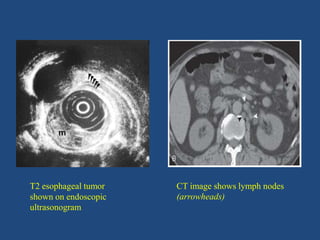

• Esophageal ultrasonography -

To look for the depth of the tumor, involvement of

nodes, cardia and left lobe of the liver. Nodes smaller

than 5 mm can be very well visualized by EUS which

may be missed in CT scan.

• CT scan –

To look for local extension, nodal status,

perioesophageal, diaphragmatic, pericardial vascular

infiltration, obliteration of mediastinal fat and status of

tracheobronchial tree in case of upper third growth.

T2 esophageal tumor

shown on endoscopic

ultrasonogram

CT image shows lymph nodes

(arrowheads)